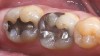

Mechanical properties are low, with flexural strength usually from 60 MPa to 70 MPa. Thus, they tend to be employed as veneer materials for metal or ceramic substructures, as well as for veneers, using either a refractory die technique or platinum foil. The microstructure of a glass is shown in Figure 1. This is an electron micrograph of an acid-etched glass surface. The holes indicate a second glass, which was removed by the acid. The veneer restoration uses a glassy porcelain (Figure 2A and Figure 2B).

The original materials had a fairly random size and distribution of leucite crystals with the average particle size of approximately several hundred microns. This random distribution and large particle size contributed to the material’s low fracture resistance and abrasive properties relative to enamel.8 Newer generations of materials have been developed with much finer leucite crystals (10 µm to 20 µm) and very even particle distribution throughout the glass. These materials are less abrasive and have much higher flexural strengths.9 In Figure 3, an electron micrograph of a typical feldspathic porcelain reveals a glass matrix surrounding leucite crystals. These materials are most commonly used as veneer porcelains for metal-ceramic restorations (Figure 4).

The most widely used version is the original pressable ceramic Empress® (Ivoclar Vivadent, www.ivoclarvivadent.com) (Figure 5 through Figure 6B).). A number of pressable materials with properties and microstructure similar to Empress are available. These include Finesse® (DENTSPLY, www.dentsply.com), Authentic® (Jensen, www.jensendental.com), PM™9 (Vita, www.vident.com), and OPC (Pentron, www.pentronceramics.com). A machinable version of Empress CAD (Ivoclar) designed for both CEREC® and E4D® CAD/CAM (D4D Technologies, www.e4dsky.com) systems for high-leucite ceramics has performed well clinically when used for posterior inlays and onlays, as well as anterior veneer and crown restorations.9-14 Paradigm™ C porcelain block (3M ESPE, www.3mespe.com) has similar properties. Machinable and pressable systems have much higher fracture resistance than powder/liquid systems and have shown excellent clinical results for posterior inlay and onlay applications and anterior veneer and crown restorations.2-7,10-14